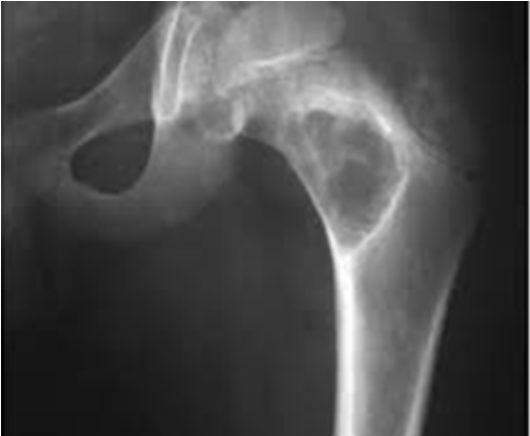

Остеопороз. Проявляется видимым снижением плотности костной ткани. На рентгенограммах принимает вид участков затемнения.

Некроз. Участок некроза кажется более плотным, из-за чего выделяется на фоне окружающих тканей.

Деструкция. На рентгенограмме имеет вид костного дефекта. Свежие деструктивные очаги имеют неровные контуры, застарелые – ровные и уплотненные.

Деформирующий остеоартроз. На ранних стадиях рентгенологические признаки отсутствуют. Позже о патологии говорит сужение суставной щели.